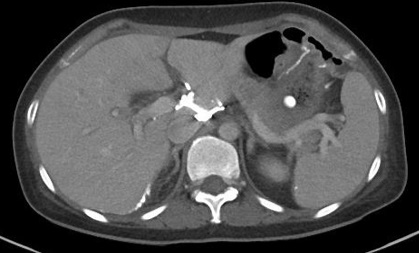

肾癌肾切除后乳糜腹水 Chylous ascites after nephrectomy for renal malignancy

流入淋巴管栓塞

56岁 男性 肾癌根治术后乳糜腹水 | ||||||||||||||||||||||||||||||||||||||||||||||||||||||||||||||||||||||||||||||||||||||||||||||||||||||||||||||||||||||||||||||||||||||||||||||||||||||||||||||||||||||||||